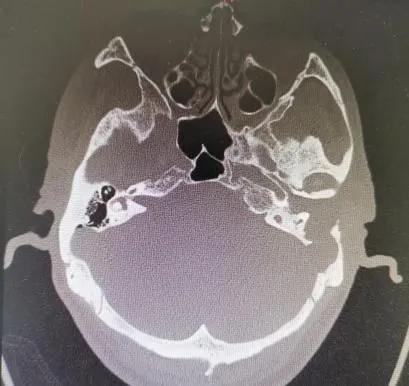

当地医院骨科将武先生诊断为颈椎病,后来又辗转几家医院仍无法确定病因……后来武先生住进郑州市中心医院神经外科,头颅MRI显示:左侧颞叶脑脓肿、中耳乳突炎。原来是因剧烈头痛再发“颅内感染”。

既没有基础疾病,也没有外伤病史,好端端的怎么会反复颅内感染呢?看着武先生的影像片子,神经外科医师突然想到:会不会是中耳炎侵袭到颅内导致的颅内脓肿和感染呢?!随即,该医师迅速联系耳鼻咽喉头颈外科主任李玉杰,详细询问病史、查体和全面查看影像学片子。

李玉杰主任认为,这是一例巨大“中耳胆脂瘤”破坏周围骨质后,蔓延至颅内引发的严重颅内外并发症。病根在中耳,必须尽快手术!

病因找到了,然而手术却是个难题!术前患者因中耳胆脂瘤导致的周围骨质破坏先后引起乙状窦血栓性静脉炎、硬脑膜缺损、脑膜炎、脑脓肿、迷路炎、面肌痉挛等多种颅内、外并发症,手术过程存在着巨大的风险,手术难度大,风险极高!